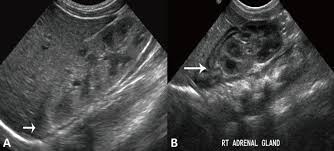

Kidney Ultrasound Adrenal Glands. It s hard to see normal adult adrenals on ultrasound despite being near the kidneys review of the adrenals in an adult is not part of the routine kidney ultrasound. An outer cortex and an inner medulla.

Ct scans also show the organs near the adrenal glands as well as lymph nodes and distant organs. 190 layers of adrenal gland. It s hard to see normal adult adrenals on ultrasound despite being near the kidneys review of the adrenals in an adult is not part of the routine kidney ultrasound.

Details of the adrenal glands. High resolution real time sonography allows visualization of normal adrenal glands in 71 92 of adults. The normal ascent of the kidneys allows the organs to take their place in the abdomen below the adrenal glands. The left adrenal gland is imaged by a posterolateral approach in coronal plane through the long axis of the left kidney.